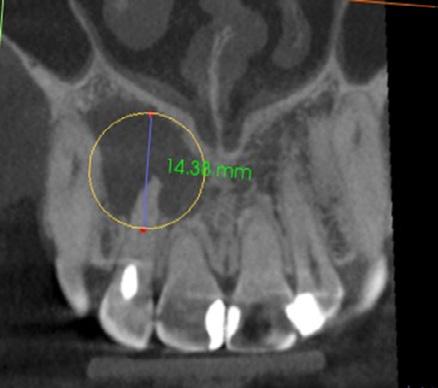

Issuu converts static files into: digital portfolios, online yearbooks, online catalogs, digital photo albums and more. Sign up and create your flipbook.